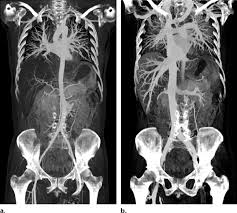

Post-mortem CT (LIVE)

Webinar

Starts Mar 26 at 9:00 AM GMT